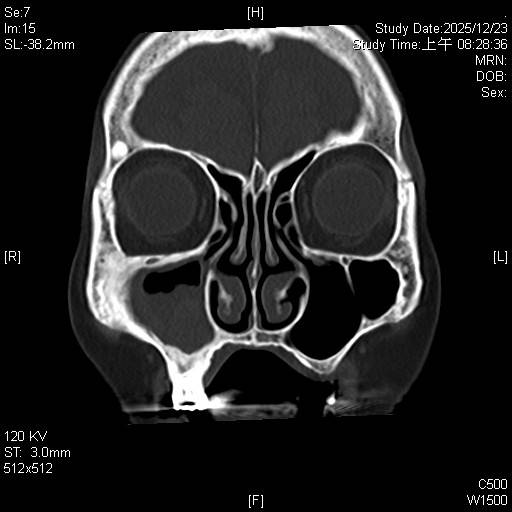

東元綜合醫院耳鼻喉科詹健暘主治醫師表示,阿嬤經過診斷為「慢性鼻竇炎,伴隨黴菌性鼻竇炎(fungal sinusitis)」。這類疾病在台灣潮濕的氣候環境下相當常見,黴菌塊(或稱黴菌球)常堆積在單側上頜竇,屬於非侵襲性黴菌感染,但在鼻竇內會不斷堆積成團塊,典型的表現為單側或局部鼻竇阻塞、鼻涕倒流,甚至頭痛。

考量高齡病人,手術治療面臨最大的挑戰在於「麻醉風險」。90歲長輩通常伴隨心血管或肺部功能退化,全身麻醉後的甦醒及併發症風險較高。所以經詳細評估後,決定採取局部麻醉下的「鼻竇內視鏡微創手術(functional endoscopic sinus surgery, FESS)」來治療。

耳鼻喉科詹健暘醫師指出,黴菌性鼻竇炎的「黃金標準治療」是透過手術徹底清除黴菌團塊及發炎組織,恢復鼻竇通氣與引流。若單純使用藥物治療,往往難以根治,且長期鼻涕倒流可能引發慢性咳嗽或影響呼吸道健康。

鼻竇內視鏡微創手術的優點在於,沒有外部傷口,開擴鼻竇開口操作,不破壞外觀;安全性高,避免全身麻醉對心肺功能的風險;恢復迅速,手術精準清除發炎組織與黴菌塊,出血量少,術後阿嬤恢復良好無併發症、鼻涕倒流緩解,恢復更好的生活品質。

詹健暘醫師解釋,黴菌球經內視鏡手術徹底清除後,通常不需額外服用抗黴菌藥物,且復發率極低。建議鼻竇炎病人在術後可維持規律的鼻腔鹽水沖洗,並定期回診追蹤,以確保鼻腔黏膜健康。

詹健暘醫師表示,此成功案例顯示,年齡並非微創手術的絕對禁忌。尤其高齡長輩若有長期鼻塞、鼻涕倒流、或黃膿鼻涕等症狀,還是應尋求專業耳鼻喉科醫師評估,選擇最安全的治療方案來提升晚年生活品質。